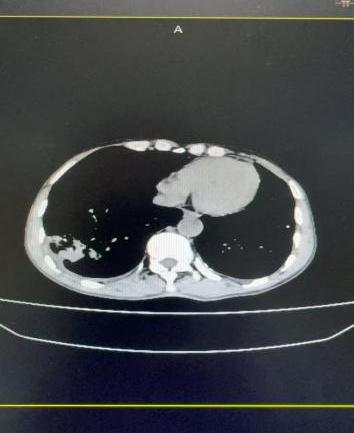

案例二:魏先生,64岁,肾恶性肿瘤术后肝、肺转移。2025年11月3日,在DSA引导及局麻下行经导管支气管动脉联合肝动脉造影、栓塞+灌注化疗术,实现多部位协同治疗。

支气管动脉造影                                                                    肝动脉造影